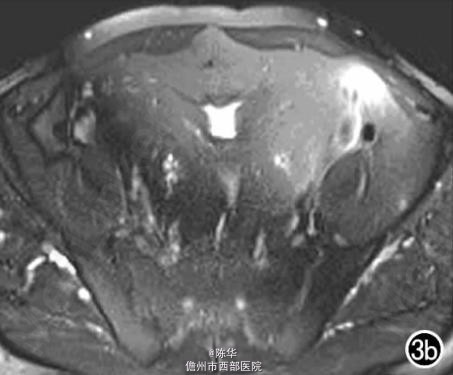

腹部B超示双肾增大,双肾慢性肾病声像;双肾中度积液伴双输尿管上段扩张。 IVPshi双侧输尿管中或下段梗阻。 膀胱造影:经尿道置管后,注射对比剂充盈膀胱,膀胱下半部先充盈,继续灌注对比剂后见膀胱完全显影,膀胱形态异常,呈“倒葫芦状”(图1)。 CT增强扫描行延迟期 MPR重组,见双侧肾盂、肾盏扩张积液;双侧输尿管纡曲、扩张,下端呈鸟嘴样变窄;膀胱变形、体积减小(图2); MRI平扫示双侧肾盂、肾盏扩张积液,双侧输尿管扩张并下端鸟嘴样变窄,盆腔内多量脂肪沉积,分布于膀胱、直肠周围,T1WI、T2WI呈明显高信号,T2WI抑脂像呈稍高信号,膀胱受压变形、体积减小(图3a~c); MRU示双侧肾盂肾盏扩张、积液,双侧输尿管显著纡曲、扩张,下端鸟嘴样变窄,管壁光整,膀胱变形、体积较小、位置抬高(图3d)。